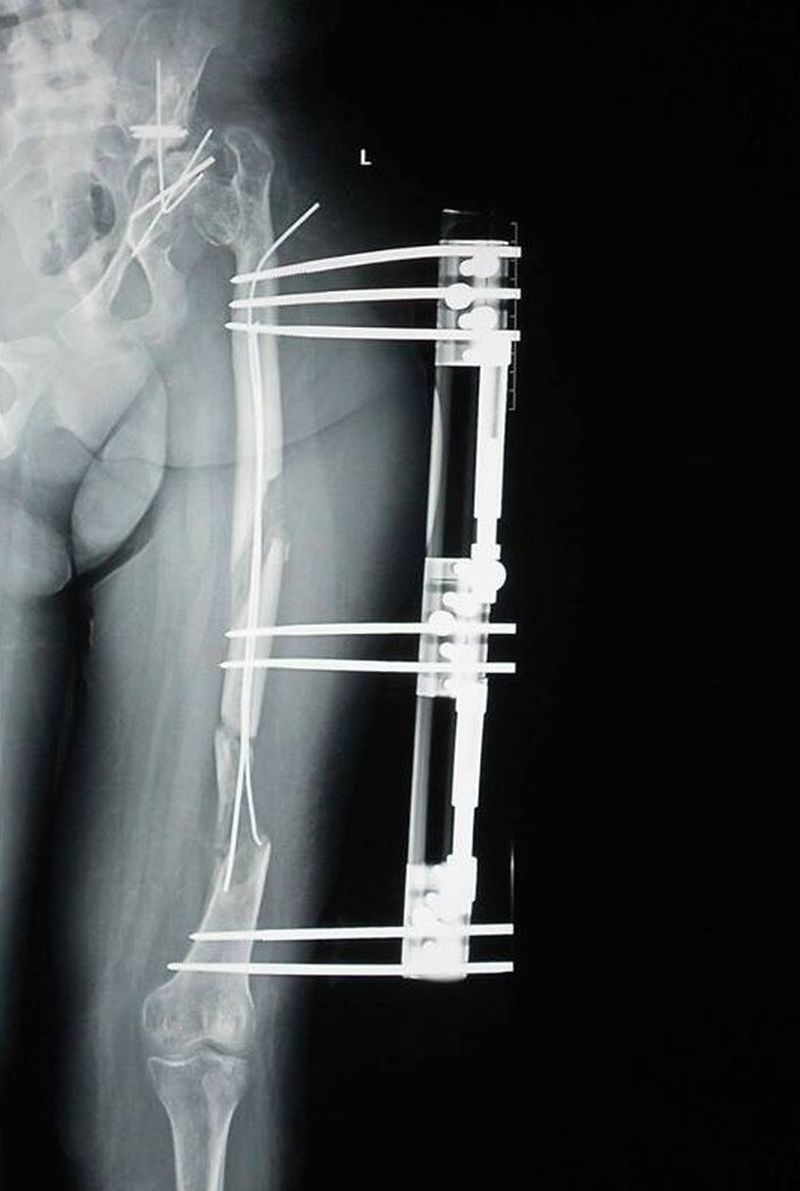

Verdictul medicilor nu a fost deloc unul imbucurator: fata are pareza de nervul femural si la cel peronier profund. Mama tinerei spune ca aceste probleme au fost provocate de fixatorul extern folosit de doctorul Burnei, pentru alungirea membrului stang, care ramasese cu 8 centimetri mai scurt decat cel drept. Fixatorul folosit de Gheorghe Burnei e alcatuit dintr-o tija metalica aplicata pe picior, care fixeaza osul printr-un soi de suruburi care patrund direct prin carnea pacientului.

Amira a avut, in total, 14 gauri in picior.